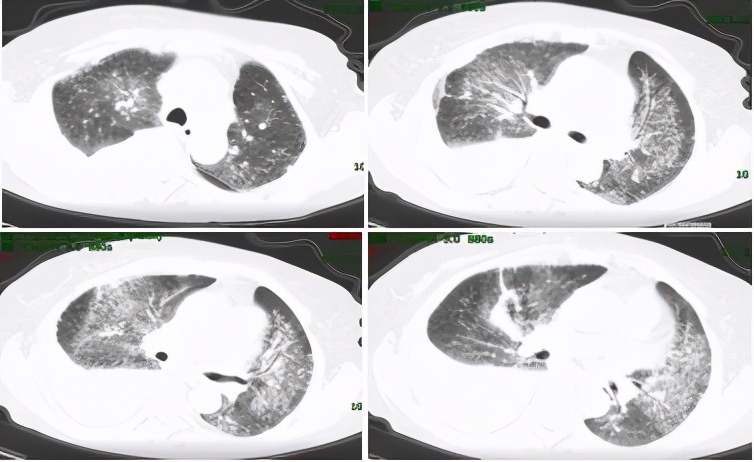

该患者到底是副肿瘤性风湿病综合征,还是肿瘤合并系统性硬化呢?这需要在进一步的治疗中验证。由于该患者及家属不愿行盆腔占位活检,放弃了放化疗等肿瘤相关治疗,因口服激素及复方环磷酰胺后呼吸困难好转,愿意继续行系统性硬化病的相关治疗:泼尼松片(40mg qd,逐渐缓慢减量),复方环磷酰胺片100mg qd (长期口服未减量),乙酰半胱氨酸600mg tid,百令胶囊4颗 tid。经上述治疗后,患者呼吸困难进一步好转,后于治疗后约1个月及3个月后复查胸部CT提示肺部病灶减少,胸水逐渐减少至基本吸收。原则上副肿瘤综合征肿瘤治疗后风湿病表现才明显好转,只是抗风湿治疗好转并不能证明是副肿瘤综合征。通过治疗反应,考虑患者为肿瘤伴发系统性硬化可能性大。

图5:复查胸部CT(2017-03-16)肺部病灶吸收,胸水减少

图6:复查胸部CT(2017-05-26)肺部病灶进一步吸收,胸水基本吸收